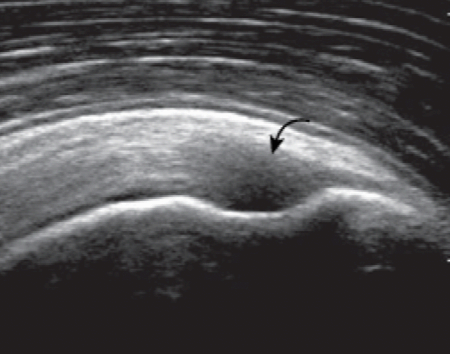

목차 반응형어깨 검사를 위하여 환자는 의자의 발이 고정된 등받이 없는 회전의자에 앉고, 검사자는 이동성이 좋은 바퀴 달린 의자에 앉는다. 환자의 왼쪽어깨를 검사할 때에는, 환자가 초음파기기를 향하여 앉고, 검사자는 초음파기기와 환자사이에 엇비슷하게 앉는다. 오른쪽 어깨를 검사할 때에는, 검사자가 기계를 향하여 앉고, 환자는 검사자를 엇비슷하게 마주 보고 앉는다. 어깨의 초음파 검사는 적어도 10 Mhz 이상의 주파수를 가진 탐촉자를 사용한다. 환자의 체격이 좋고 비대하거나, 어깨뼈오목테두리(glenoid labrum)등, 어깨 깊은 곳에 있는 구조물을 보려면 낮은 주파수의 탐촉자를 쓰기도 한다. 검사 항목을 빠뜨리지 않고 검사를 하기 위하여, 다음에서 설명하는 검사 순서에 따라 단계별로 하는 것이 중요하다. 다른 관절에서는 필요한 부분만 골라서 중점적으로 검사하기도 하지만, 어깨에서는 통증의 원인이 애매하고, 또 다른 부위의 병변에 의한 통증이 어깨에 연관통증(referred pain)을 나타낼 수 있고, 또 어깨의 질병이 다른 부위에 연관통증을 일으킬 수 있기 때문이다. 물론, 통증이나 증상이 있는 곳을 추가로 검사하는 것은 필수적이다. 자세 1. 두 갈래 근 긴 힘줄환자는 검사받는 팔의 손바닥이 위를 향하게 하여 손등을 환자의 넙다리에 놓는다. 이 자세를 중립 상태라고 한다. 탐촉자를 가로축 방향으로 어깨의 앞쪽에 놓으면 두 갈래 근 긴 힘줄(long head of biceps brachii tendon)이 두 갈래 근고랑에 놓인 것을 볼 수 있다.  두갈래근 긴힘줄 초음파 영상(short axis) 이 자세는 어깨의 앞쪽에서 중요한 표식자(landmark)인 두 갈래 근고랑의 움직임을 보면서 회전근띠를 검사하기에 좋다. 탐촉자를 피부에 대면 두갈래근 긴 힘줄이 정상인데도 검고 낮은 에코로 보인다. 이를 비등방성(anisotropy) 허상이라 한다. 그 이유는 힘줄이 아래로 갈수록 비스듬하게 기울기를 가지면서 깊어지기 때문이다. 탐촉자를 힘줄에 대해 90도가 되도록 조절하면 비등방성이 사라지고 힘줄은 높은 에코로 바뀐다. 가로축 방향에서 위, 아래로 두 갈래 근 긴 힘줄을 따라가면서 검사한 뒤에 탐촉자를 90도로 돌려서 세로축 방향에서 검사한다. 마찬가지로 입사 초음파가 힘줄에 대해 직각이 되도록 탐촉자의 각도를 조절하면서 검사한다. 세로축 방향에서 작은 거 친면은 특징적으로 세모꼴로 보이는데 그 바로 바깥쪽의 두 갈래 근고랑에는 두 갈래 근 긴 힘줄이 세로로 길게 놓여있다.  두갈래근 긴힘줄 초음파 영상(longitudinal) 자세 2. 어깨밑근과 두갈래근 긴 힘줄의 탈구자세 1 '중립자세'에서 탐촉자를 어깨 앞쪽에 가로축 방향으로 놓으면 두 갈래 근 긴 힘줄(biceps tendon)보다 안쪽으로 어깨밑 근(subscapularis)이 보이는데, 어깨밑근의 긴 축영상(long-axis images)이다. 이 자세에서 어깨밑근은 심한 비등방성 때문에 매우 검게 보인다. 환자의 팔을 바깥돌림(external rotation)하면 어깨밑근이 입사 초음파에 대해 수직으로 놓이게 되면서 비등방성이 사라지게 되고 정상적인 높은 에코로 바뀐다. 이 자세에서 탐촉자를 위, 아래로 움직여서 어깨밑근이 작은 거 친면에 넓게 붙는 것을 본다. 팔을 안-바깥돌림(internal and external rotation)하면서 두갈래근 긴 힘줄이 두 갈래 근고랑에서 벗어나지 않음을 관찰한다. 두 갈래 근 긴 힘줄의 부분이탈이나 어긋남(subluxation or dislocation)이 팔의 바깥돌림에서만 나타날 수 있다. 탐촉자를 90도 돌려 세로로 놓으면, 탐촉자는 어깨밑근의 주행방향에 대해 90도 각도로 놓이게 되고, 어깨밑근을 짧은 축영상(short-axis images)에서 검사한다. 어깨밑근의 짧은 축영상에서, 높은 에코의 힘줄다발(tendon bundle) 사이사이에 낮은 에코의 근육이 줄무늬(striation)로 보이는데 이는 정상소견이며, 공간복합기능(spatial compound function)이 없는 초음파기기에서는 대조도가 더 뚜렷하게 보인다. 자세 3. 봉우리빗장관절 및 봉우리밑-세 모근밑 윤활주머니봉우리빗장관절(acromioclavicular joint)은 탐촉자를 빗장뼈(clavicle) 먼쪽(distal)에 빗관상면(coronal-oblique plane)으로 놓고 손으로 만지면서 그 위치를 찾거나, '자세 1' 에서처럼 가로축 방향으로 놓은 탐촉자를 그대로 어깨 위로 옮기면서 찾아간다. 관절을 이루는 두 뼈는 높은 에코로 보이고, 관절강(joint cavity)은 낮은 에코로 나타난다. 탐촉자를 관절 위에 놓은 상태에서, 탐촉자를 잡지 않은 검사자의 반대 손(free hand)으로 환자의 팔(검사받는 쪽)을 잡고 당기면서 검사하면, 관절의 이완(laxity)을 알 수 있다. 다른 방법은 환자의 손(검사받는 쪽)을 반대편 어깨 위로 올려서 앞뒤로 움직여보면 관절강이 넓어지는 것을 알 수 있다. 탐촉자를 바깥쪽으로 좀 더 옮기면 깊은 부위에 위팔뼈(humerus)의 큰 거 친면이 보이는데, 이때 봉우리밑 -세 모근밑 윤활주머니(subacromial -subdeltoid bursa)의 아래쪽(dependent portion)에 고인 액체를 관찰할 수 있다.  subacromial -subdeltoid bursa 자세 4. 가시아래근, 작은 원근, 뒤쪽어깨뼈 오목테두리환자가 의자에 앉은 채로 180도 돌면, 검사자는 환자의 어깨 뒤쪽을 보면서 검사하게 된다. 처음에는 환자의 손바닥을 위로 가게 한 중립상태에서 검사한다. 탐촉자를 어깨 뒤에서 위팔뼈머리(humeral head) 위치에서 가로축 방향으로 놓은 다음 가시아래근(infraspinatus)의 주행을 따라 탐촉자의 바깥쪽 끝을 약간 위로 비스듬하게 기울이면, 가시아래근의 힘줄이 근육의 가운데에서 나와서 위팔뼈머리에 붙는 곳을 볼 수 있는데, 이 영상은 가시아래근의 긴 축영상이다. 탐촉자를 아래로 약간 옮기면 작은 원근(teres minor)이 보이는데, 가시아래근 힘줄은 근육의 가운데에 있는데 반해, 작은원근 힘줄은 근육에 대해 표재성으로 있다. 탐촉자를 90도 돌려서 세로축 방향으로 놓으면 가시아래근과 작은 원근의 짧은 축 영상이 얻어지는데, 어깨뼈몸 쪽(proximal scapula)에서 근육-힘줄이음부가 보이고, 이곳에서 가시아래근의 크기는 작은 원근의 2배 정도이다. 탐촉자를 바깥쪽으로 비스듬히 옮기면, 근육은 점차 얇아지고, 힘줄이 큰 거 친면에 붙는 것을 볼 수 있다. 다른 방법으로는 어깨뼈가시(scapular spine)를 손으로 만져서 확인한 다음, 탐촉자를 세로로 spine에 놓고 아래쪽으로 옮기는데, 가시 바로 아래 놓인 것이 가시아래근이다. 탐촉자를 가시아래근의 주행을 따라 기울인 긴축 방향으로 놓으면, 근육 깊숙이 어깨관절의 뒤쪽을 볼 수 있는데, 뒤쪽 어깨뼈오목(glenoid)의 끝에 붙은 어깨뼈오목테두리(glenoid labrum)가 세모꼴의 높은 에코로 보인다. 팔을 안 돌림-바깥돌림하는 과정에 동적검사를 하면, 가시아래근 힘줄과 뒤테두리(posterior labrum)를 더 잘 볼 수 있다. 이 위치에서 동적검사를 하면 뒤관절오목(posterior glenohumeral joint recess)에 고인 액체를 볼 수 있고, 또 테두리 째짐(labral tear)을 찾을 수도 있다. 탐촉자를 보다 안쪽으로 약간 옮겨서 가시관절 오목패임(spino-glenoid notch)을 관찰하는 것이 중요하다. 이곳에 테두리 곁낭종(paralabral cyst)이 생기면 볼 수 있다. 팔을 바깥돌림하면 어깨위정맥(suprascapular vein)이 굵어져서 테두리 곁낭종과 비슷하게 보이므로 주의한다. 자세 5. 가시위근가시위근힘줄의 초음파 검사에서 가장 중요한 열쇠는 가시위근(supraspinatus)의 해부학을 이해하고 팔의 위치에 따른 힘줄의 변화를 아는 것이다. 팔을 중립상태로 놓은 자세에서 가시위근힘줄의 긴축영상을 얻기 위해서는 탐촉자를 거친 면위에 관상면을 따라 위치시켜야 한다. 그런데, 이곳에서 가시위근힘줄의 많은 부분은 봉우리뼈 아래에 숨어 있기 때문에 잘 볼 수 없다. 이때 환자의 팔을 안쪽돌림하고, 구부린팔꿉을 몸에 붙인 채로 환자의 손을 환자의 허리 뒤로 옮겨서 바지의 반대편 뒤호주머니에 닿게 하면, 봉우리뼈 밑에 가려진 힘줄이 뼈 밖으로 나타난다. 이자세를 크라스 자세(crass position)라고 한다. 이 자세에서는 위팔뼈머리의 큰 거 친면이 어깨의 앞쪽에 있으므로 탐촉자를 거친 면 위에 세로로 놓으면 가시위근힘줄을 긴축방향에서 검사할 수 있다. 정상 가시위근힘줄은 높은 에코의 섬유다발로 보이고, 위쪽 가장자리가 둥글고 볼록하게 보인다. 관절면 가까이에서 큰 거 친면의 힘줄 붙는 곳에서 힘줄은 아래로 둥글게 구부려지면서(curved downward) 주행하기 때문에 탐촉자의 위치도 그에 따라 각도를 조절하면서 움직여야 하며, 이때 비등방성에 의한 힘줄의 낮은 에코를 병적 소견으로 오인하면 안 된다.  supraspinatus tendon anisotropy 가시위근힘줄이 큰 거 친면에 부착하는 길이는 약 2.25cm 이므로 힘줄의 주행을 따라 탐촉자를 앞뒤로 움직이면서 관찰해야 가시위근힘줄 전체를 검사하는 것이 된다. 또 거 친면의 가장 앞쪽으로 탐촉자를 이동하면서 관절 안 두갈래근 긴 힘줄이 보일 때까지 검사하는 것이 매우 중요하다. 그래야만 가시위근힘줄이 가장 잘 손상되는 앞쪽 끝을 검사할 수 있기 때문이다. 탐촉자를 거 친면의 뒤로 이동함에 따라 위팔뼈머리의 관절면과 거 친면이 만나는 각도가 편평해지고 가시위근힘줄이 깍지 낀 손가락처럼(interdigitating) 보이면서 낮은 에코로 나타나는데, 이는 비등방성 때문이며, 이곳이 가시위근힘줄과 가시아래근힘줄이 만나는 부위이다. 가시위근힘줄을 긴축 방향에서 검사한 다음에 탐촉자를 90도 돌려서 가시위근힘줄을 짧은 축 방향에서 검사한다. 관절 안에서 위팔뼈머리가 볼록하게 높은 에코의 줄(line)로 보이고, 그 바로 바깥을 덮고 있는 관절연골은 낮은 에코로 보인다. 회전근 띠는 아주 가지런한 두께를 보이며, 마치 자동차 바퀴와 비슷하다. 이런 모양으로 보이면 가시위근힘줄을 진짜 축방향에서 제대로 검사함을 의미한다. 가시위근힘줄을 따라 긴축방향으로 탐촉자를 힘줄의 먼 쪽으로 이동한다. 관절연골이 시야에서 사라지면서, 위팔뼈머리의 거 친면이 나타난다. 이 지점에서 힘줄은 점차 가늘어지고 관절밖으로 나오게 된다. 거 친면에서 앞뒤로 3개의 힘줄부착단면(superior, middle and inferior facets)이 있는데 모양이 편평하다. 가시위근힘줄은 위쪽단면전체와 중간단면의 위 1/2에 붙는다. 가시아래근힘줄은 가시위근힘줄과 서로 섞이면서 중간단면에 붙는다. 작은 원근은 아래단면에 붙는다. 탐촉자를 더 먼 쪽으로 이동하면 거 친면이 약간 각진 모양으로 변하고, 힘줄은 점차 얇아지면서 없어진다. 비슷한 방법으로 두 갈래 근 긴 힘줄의 관절 안 부분을 관찰하면서 가시위근힘줄의 가장 앞쪽 끝을 살펴본다. 이 부위가 가시위근힘줄의 손상이 가장 많은 곳이기 때문이다. 두 갈래 근 긴 힘줄과 회전근 간격(rotator interval)은 팔을 바깥돌림한 상태에서 가장 잘 보이는데, 환자의 손바닥을 검사하는 팔 쪽의 엉덩이에 비스듬히 놓는다. 이때 거 친면은 팔을 중립상태로 했을 때와 크라스자세(crass position)를 했을 때의 중간쯤에 위치한다. 따라서 탐촉자도 반쯤 기울어진 각도로 놓는데, 이때 탐촉자가 놓인 축은 위팔뼈와 평행하게 된다.  modified crass position 탐촉자를 90도 돌려서 가시위근힘줄과 회전근간격의 앞쪽을 검사한다. Crass 자세에 비해 변형 Crass 자세는 가시위근힘줄의 앞쪽 끝을 검사하는데 가장 중요한 표식자인 두 갈래 근 긴 힘줄을 보여주는 장점이 있고, 어깨통증이 심한 환자에서 검사하기에 편리하다. 그러나 회전근띠의 크기는 크라스자세에서 긴축 방향 영상에서 측정하는 것이 더 정확할 수 있다. 거 친면의 뒤쪽에서 가시위근힘줄과 가시아래근힘줄이 만나는 부위가 가운데단면이며, 이 부위에서는 회전근띠가 약간 얇게 보일 수 있다. 자세 6. 회전근띠 부딪힘 및 유착성관절염에서 동적검사탐촉자를 어깨 위에 빗관상면으로 놓고, 큰거친면과 봉우리가 모니터에 보이도록 한다. 환자는 힘을 빼고 팔을 몸 가까이에 늘어뜨려서 손이 엎침(pronation) 상태가 되게 한다. 팔꿈치를 구부린 상태에서 환자 스스로 앞-바깥쪽으로 팔을 들어 올리게 하거나 어깨가 아플 때까지 팔을 들어 올려 보라고 환자에게 주문한다. 이렇게 팔을 움직이는 동안에 가시위근이 봉우리 아래로 부드럽게 잘 들어가고 나오는지를 관찰한다. 만약 그렇지 못하면 유착성 관절 막요(adhesive capsulitis)을 시사한다. 봉우리밑-세 모근밑 윤할주머니의 액체가 봉우리 끝에서 고이게 되면 부딪힘(impingement)을 시사하는 소견이다. 반응형